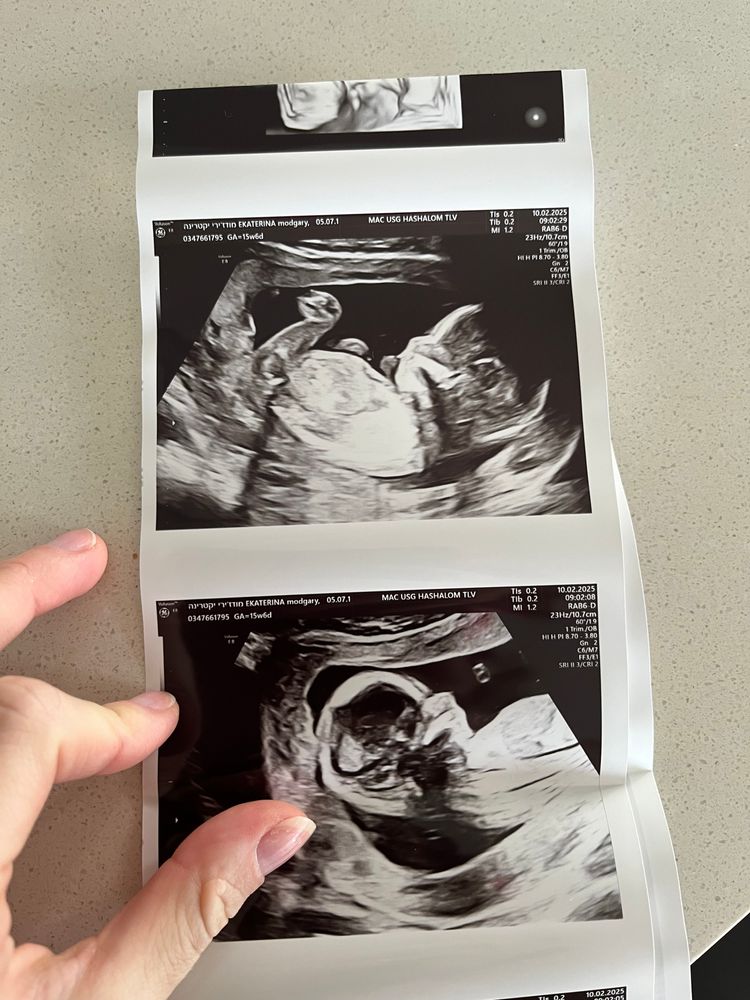

УЗИ 15 недель

УЗИ, КТГ, доплерВот мы и попали на скрининг систем, вроде бы все хорошо

Доктор несколько раз говорил, посмотрите какие губы, а я их даже на последнем 3D снимке вижу.

написал нам пол на бумажке и вчера мы узнали, что у нас будет девочка